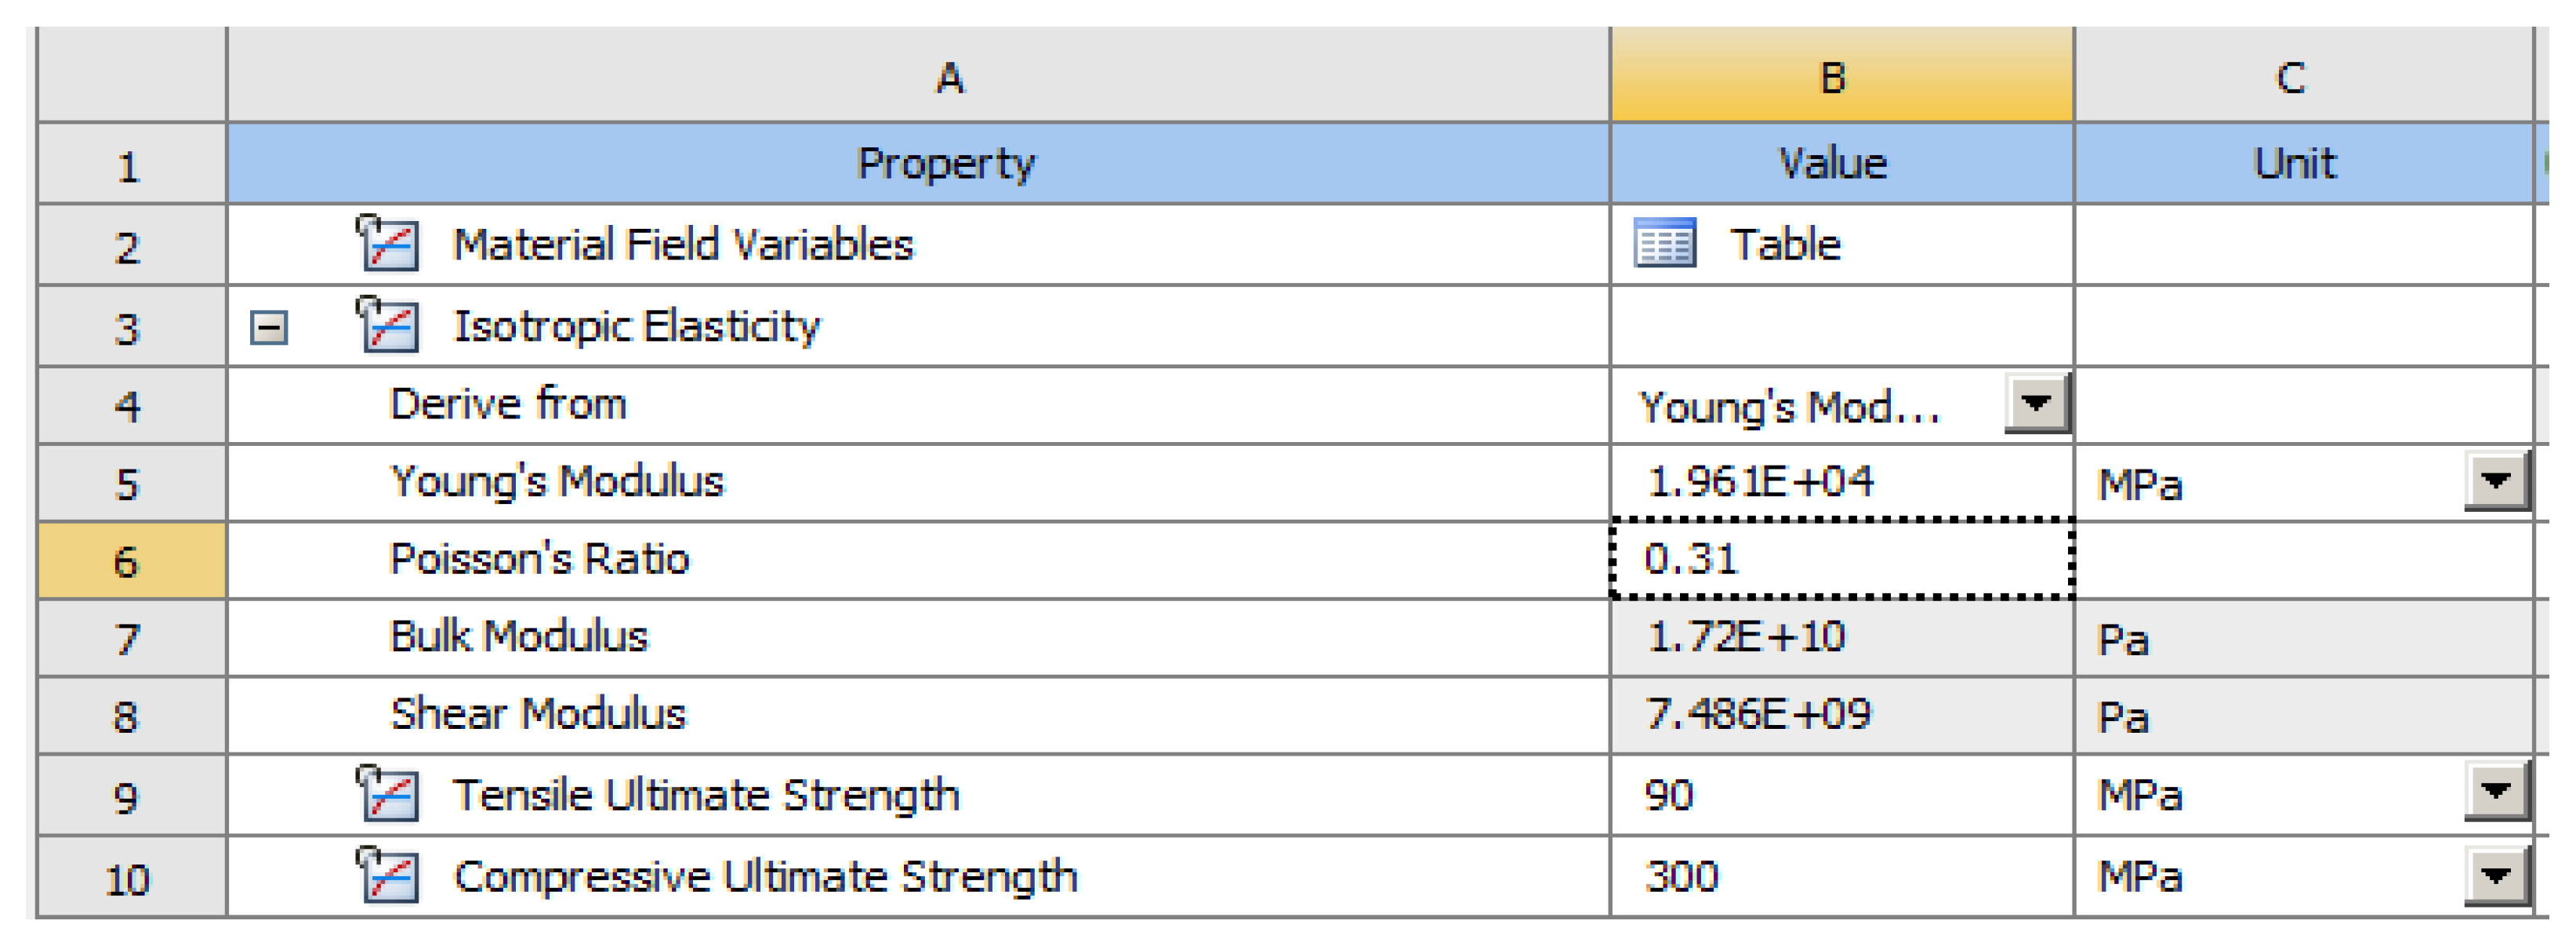

3. Finite Element Analysis (FEA) of Mandibular Right Premolars